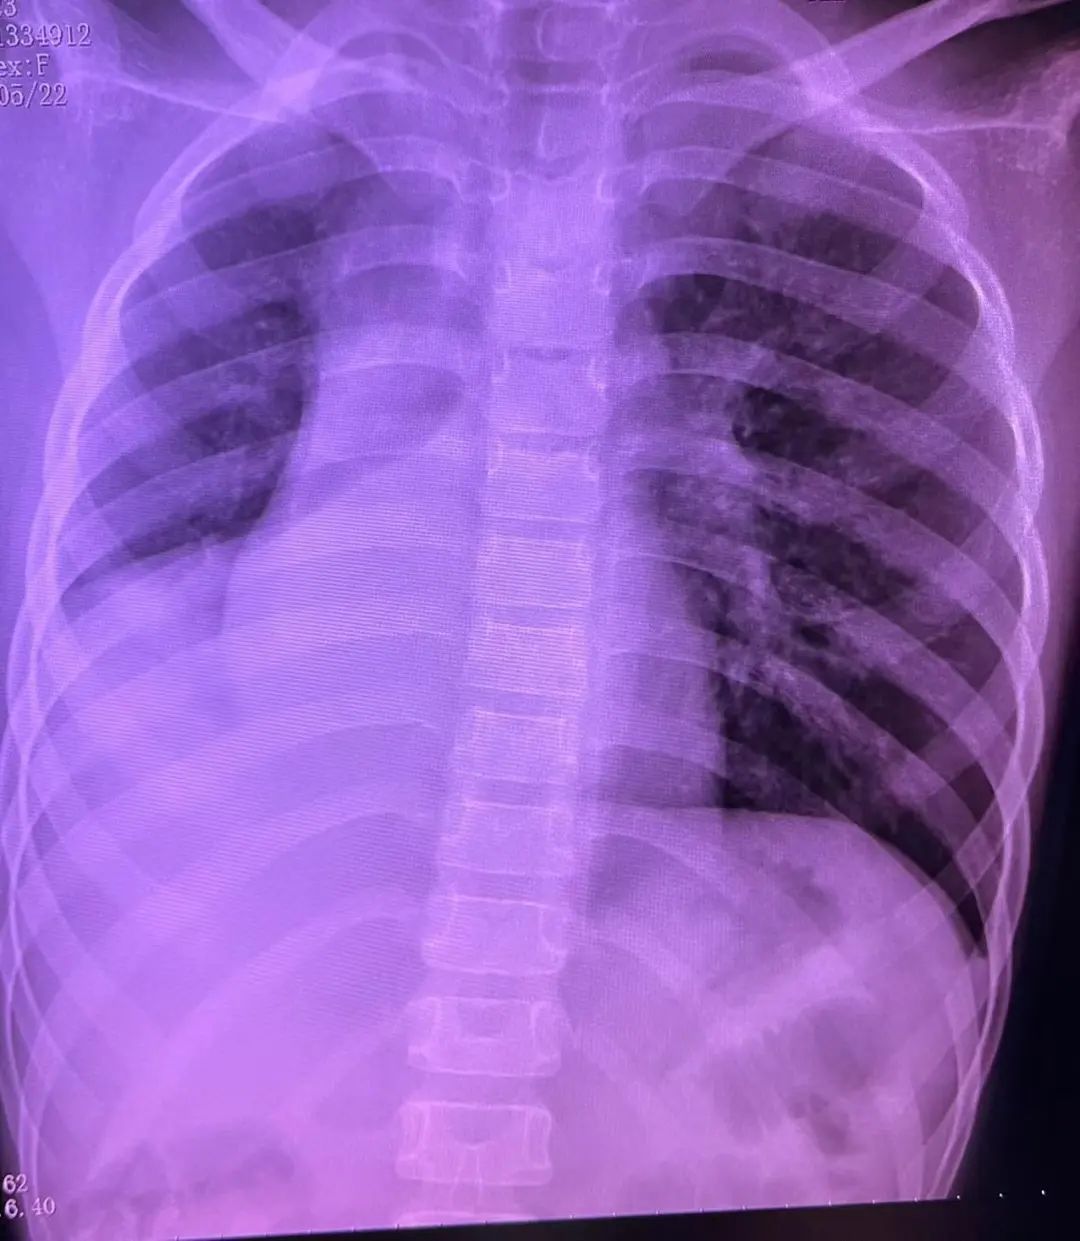

患儿外院胸部CT显示右肺上叶实变伴不张,右主支气管轻度狭窄(10月1日)

患儿是一名8岁的小女孩,9月27日因咽痛、咳嗽、咳痰及咳痰无力入住外院,既往曾出现过喘息性支气管炎。经过积极抗感染、祛痰等治疗,患儿仍出现病情持续进展,并出现了呼吸困难。10月1日胸部CT显示右肺上叶肺实变伴不张,遂转入北京清华长庚医院进一步治疗。

入我院复查胸片可见右肺不张,气管及纵隔向右移位。病情较前明显恶化。

入院次日,患儿的指尖血氧饱和度下降至88%左右,心率最高135次/分。体格检查显示患儿精神差,咳痰无力,右侧胸廓塌陷,呼吸动度消失,右肺叩实音,右肺呼吸音几乎完全消失。